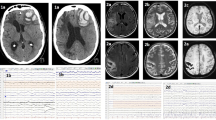

Another CEST analysis method uses a pH-weighted process to measure amide proton transfer signal intensity. In 55 patients with acute ischaemic infarct, the change in amide proton transfer signal intensity showed a good correlation (p < 0.001) with the NIHSS value and the 90-day modified Rankin scale (mRS) value (p < 0.001), which may offer a method for estimating stroke severity and long-term prognosis (Fig. 3) [93].

Conventional structural MR images (T1- and T2-weighted imaging [T1WI/T2WI]) in the first and second column, diffusion-weighted image (DWI) in the third column, and amide proton transfer weighted imaging (APTW) in the fourth column from the left. Each row corresponds to images from an individual patient with acute ischaemic infarct and differing clinical reports [93]. Figure reproduced according to the Creative Commons Attribution (CC BY) license from: Lin et al. [93]. Copyright © 2018 Lin, Zhuang, Shen, Xiao, Chen, Shen, Zong and Wu